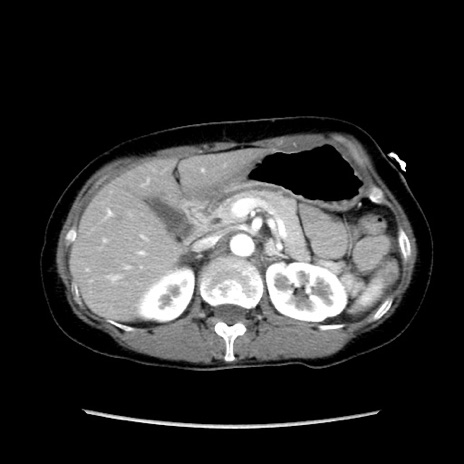

症例32(横断像)

【症例】40歳代 女性

【主訴】上腹部痛、嘔気・嘔吐

【現病歴】約9時間前頃から急に上腹部痛、嘔気、嘔吐が出現。改善しないため救急要請。

【既往歴】子宮頚癌(広汎子宮全摘術、放射線療法)、腸閉塞

【身体所見】腹部:平坦、軟、腸雑音亢進、上腹部を中心に腹部全体に圧痛あり。

【データ】WBC 8400、CRP 0.03